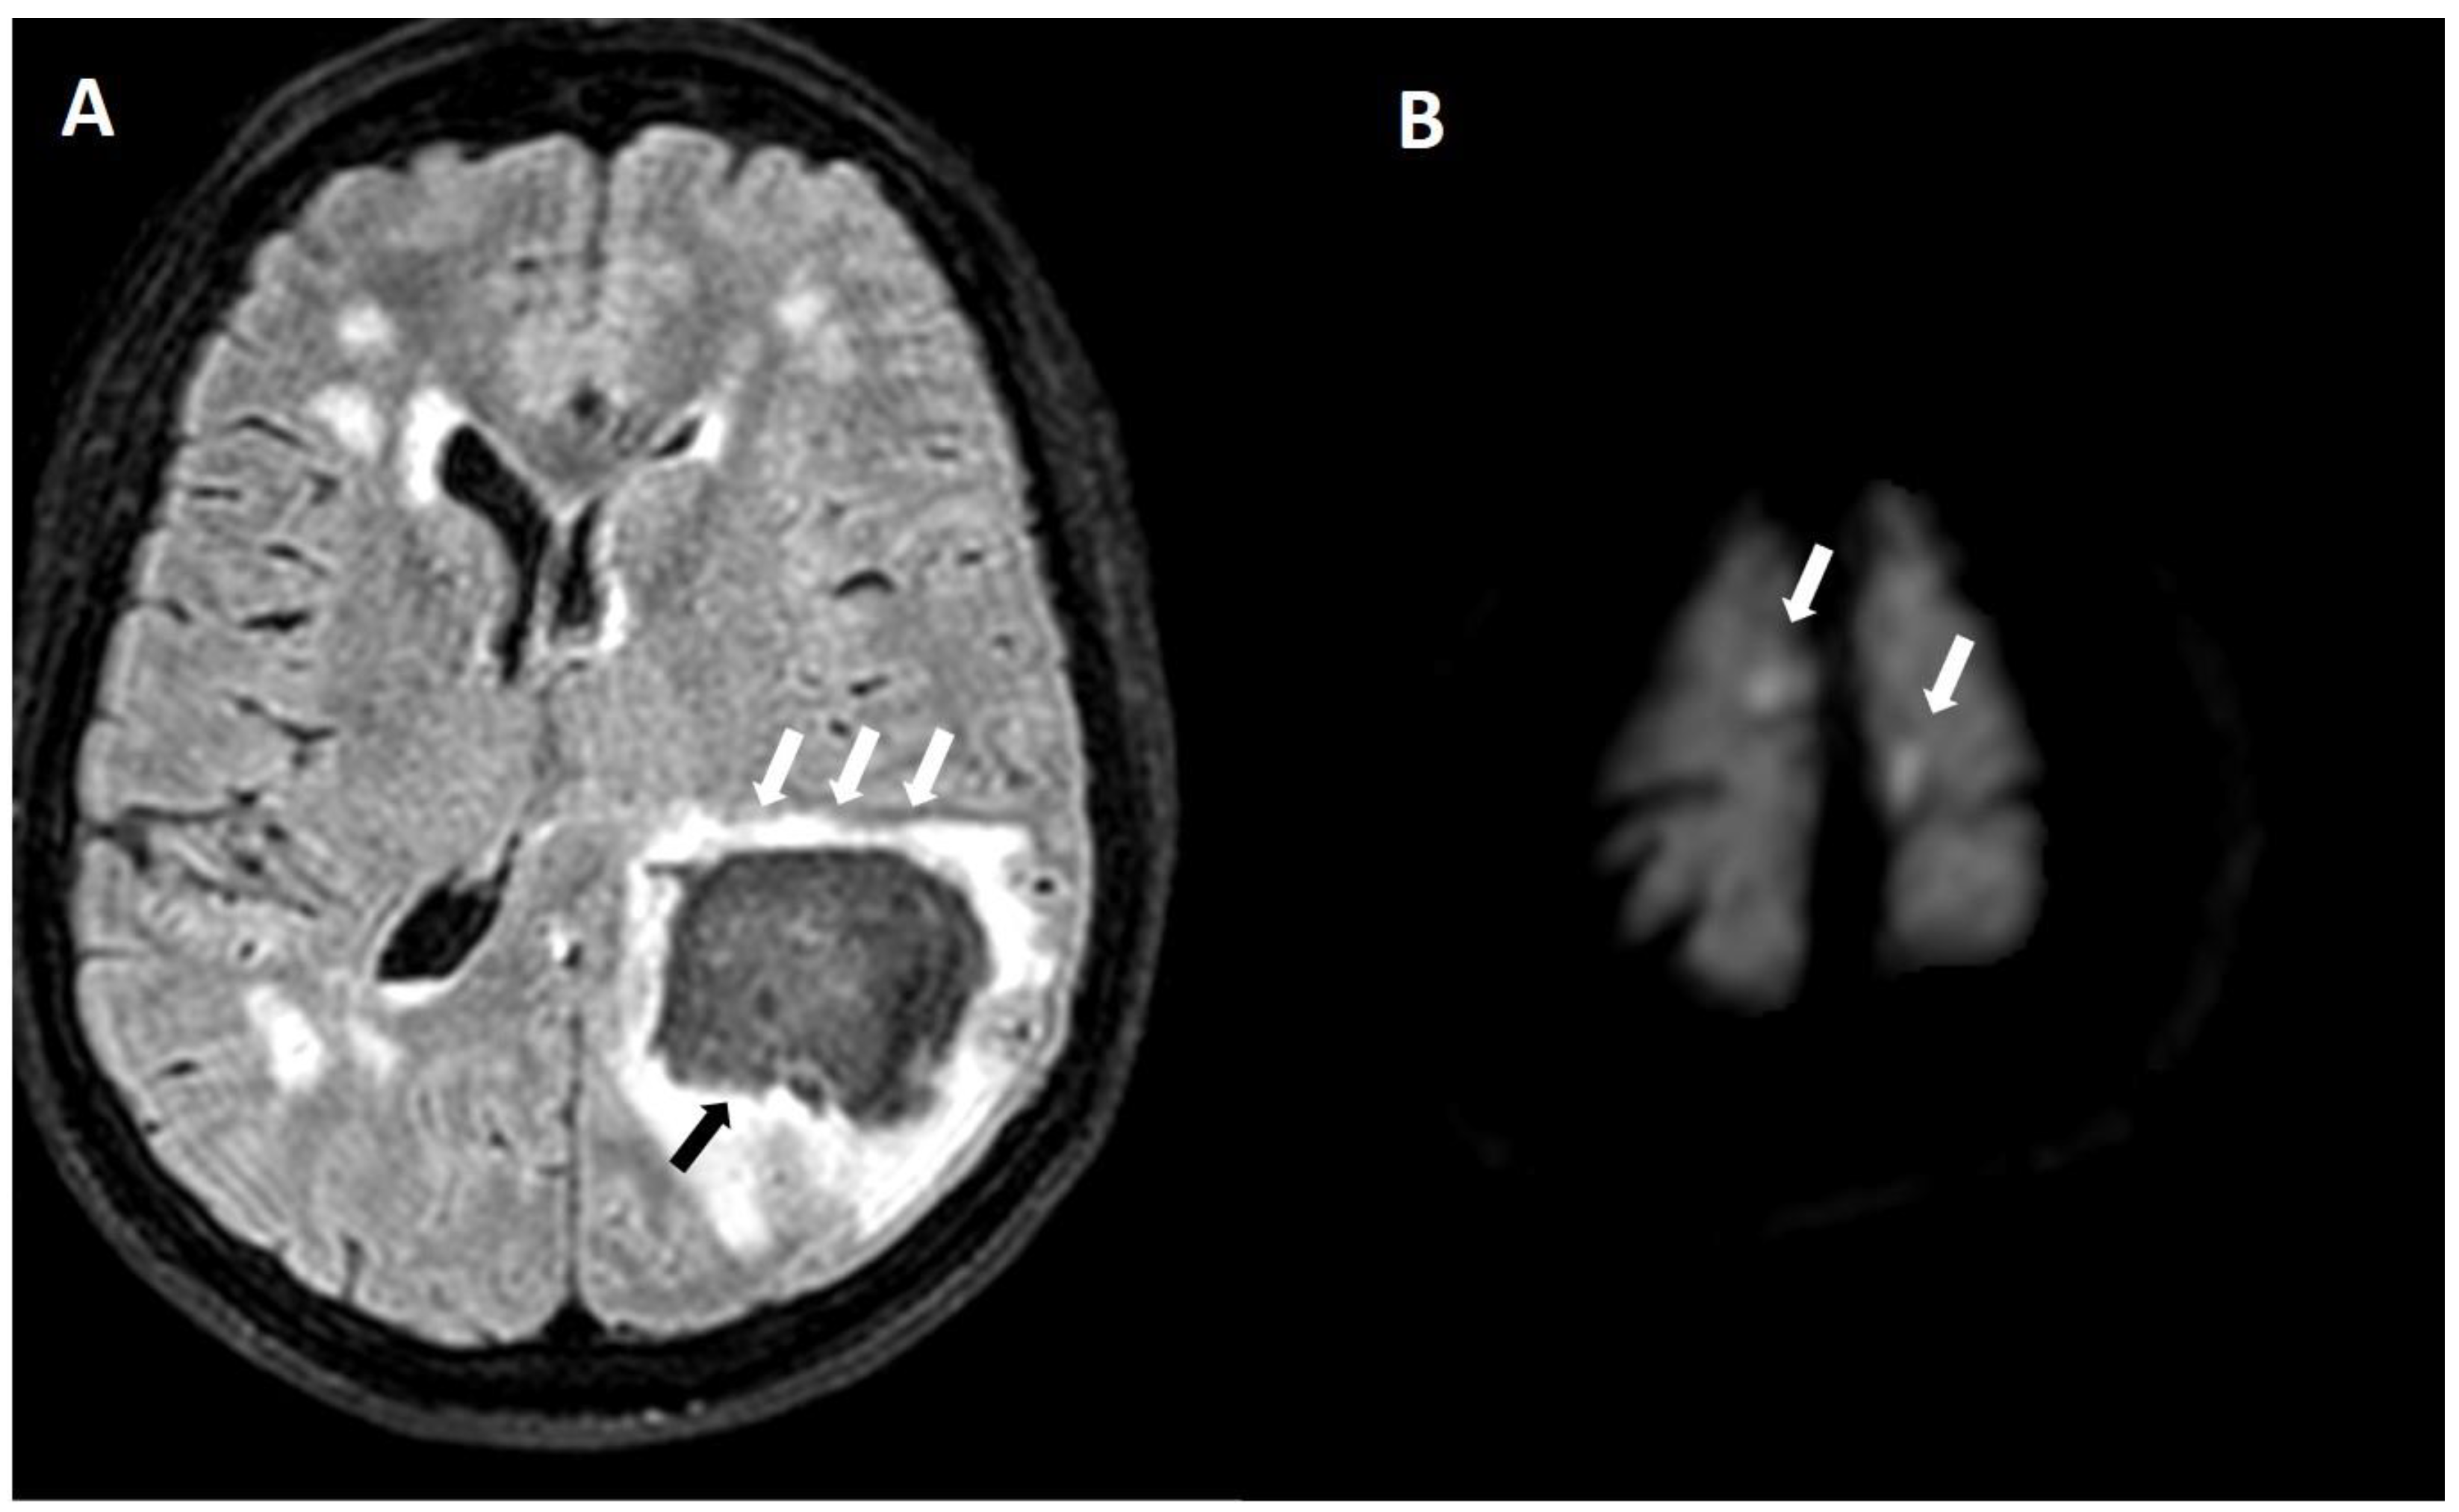

5.1. Hemorrhagic Lesions

5.1.1. Lobar Hemorrhages

5.1.3. Convexity Subarachnoid Hemorrhage

5.1.4. Cortical Superficial Siderosis

6.3. DWI Lesions